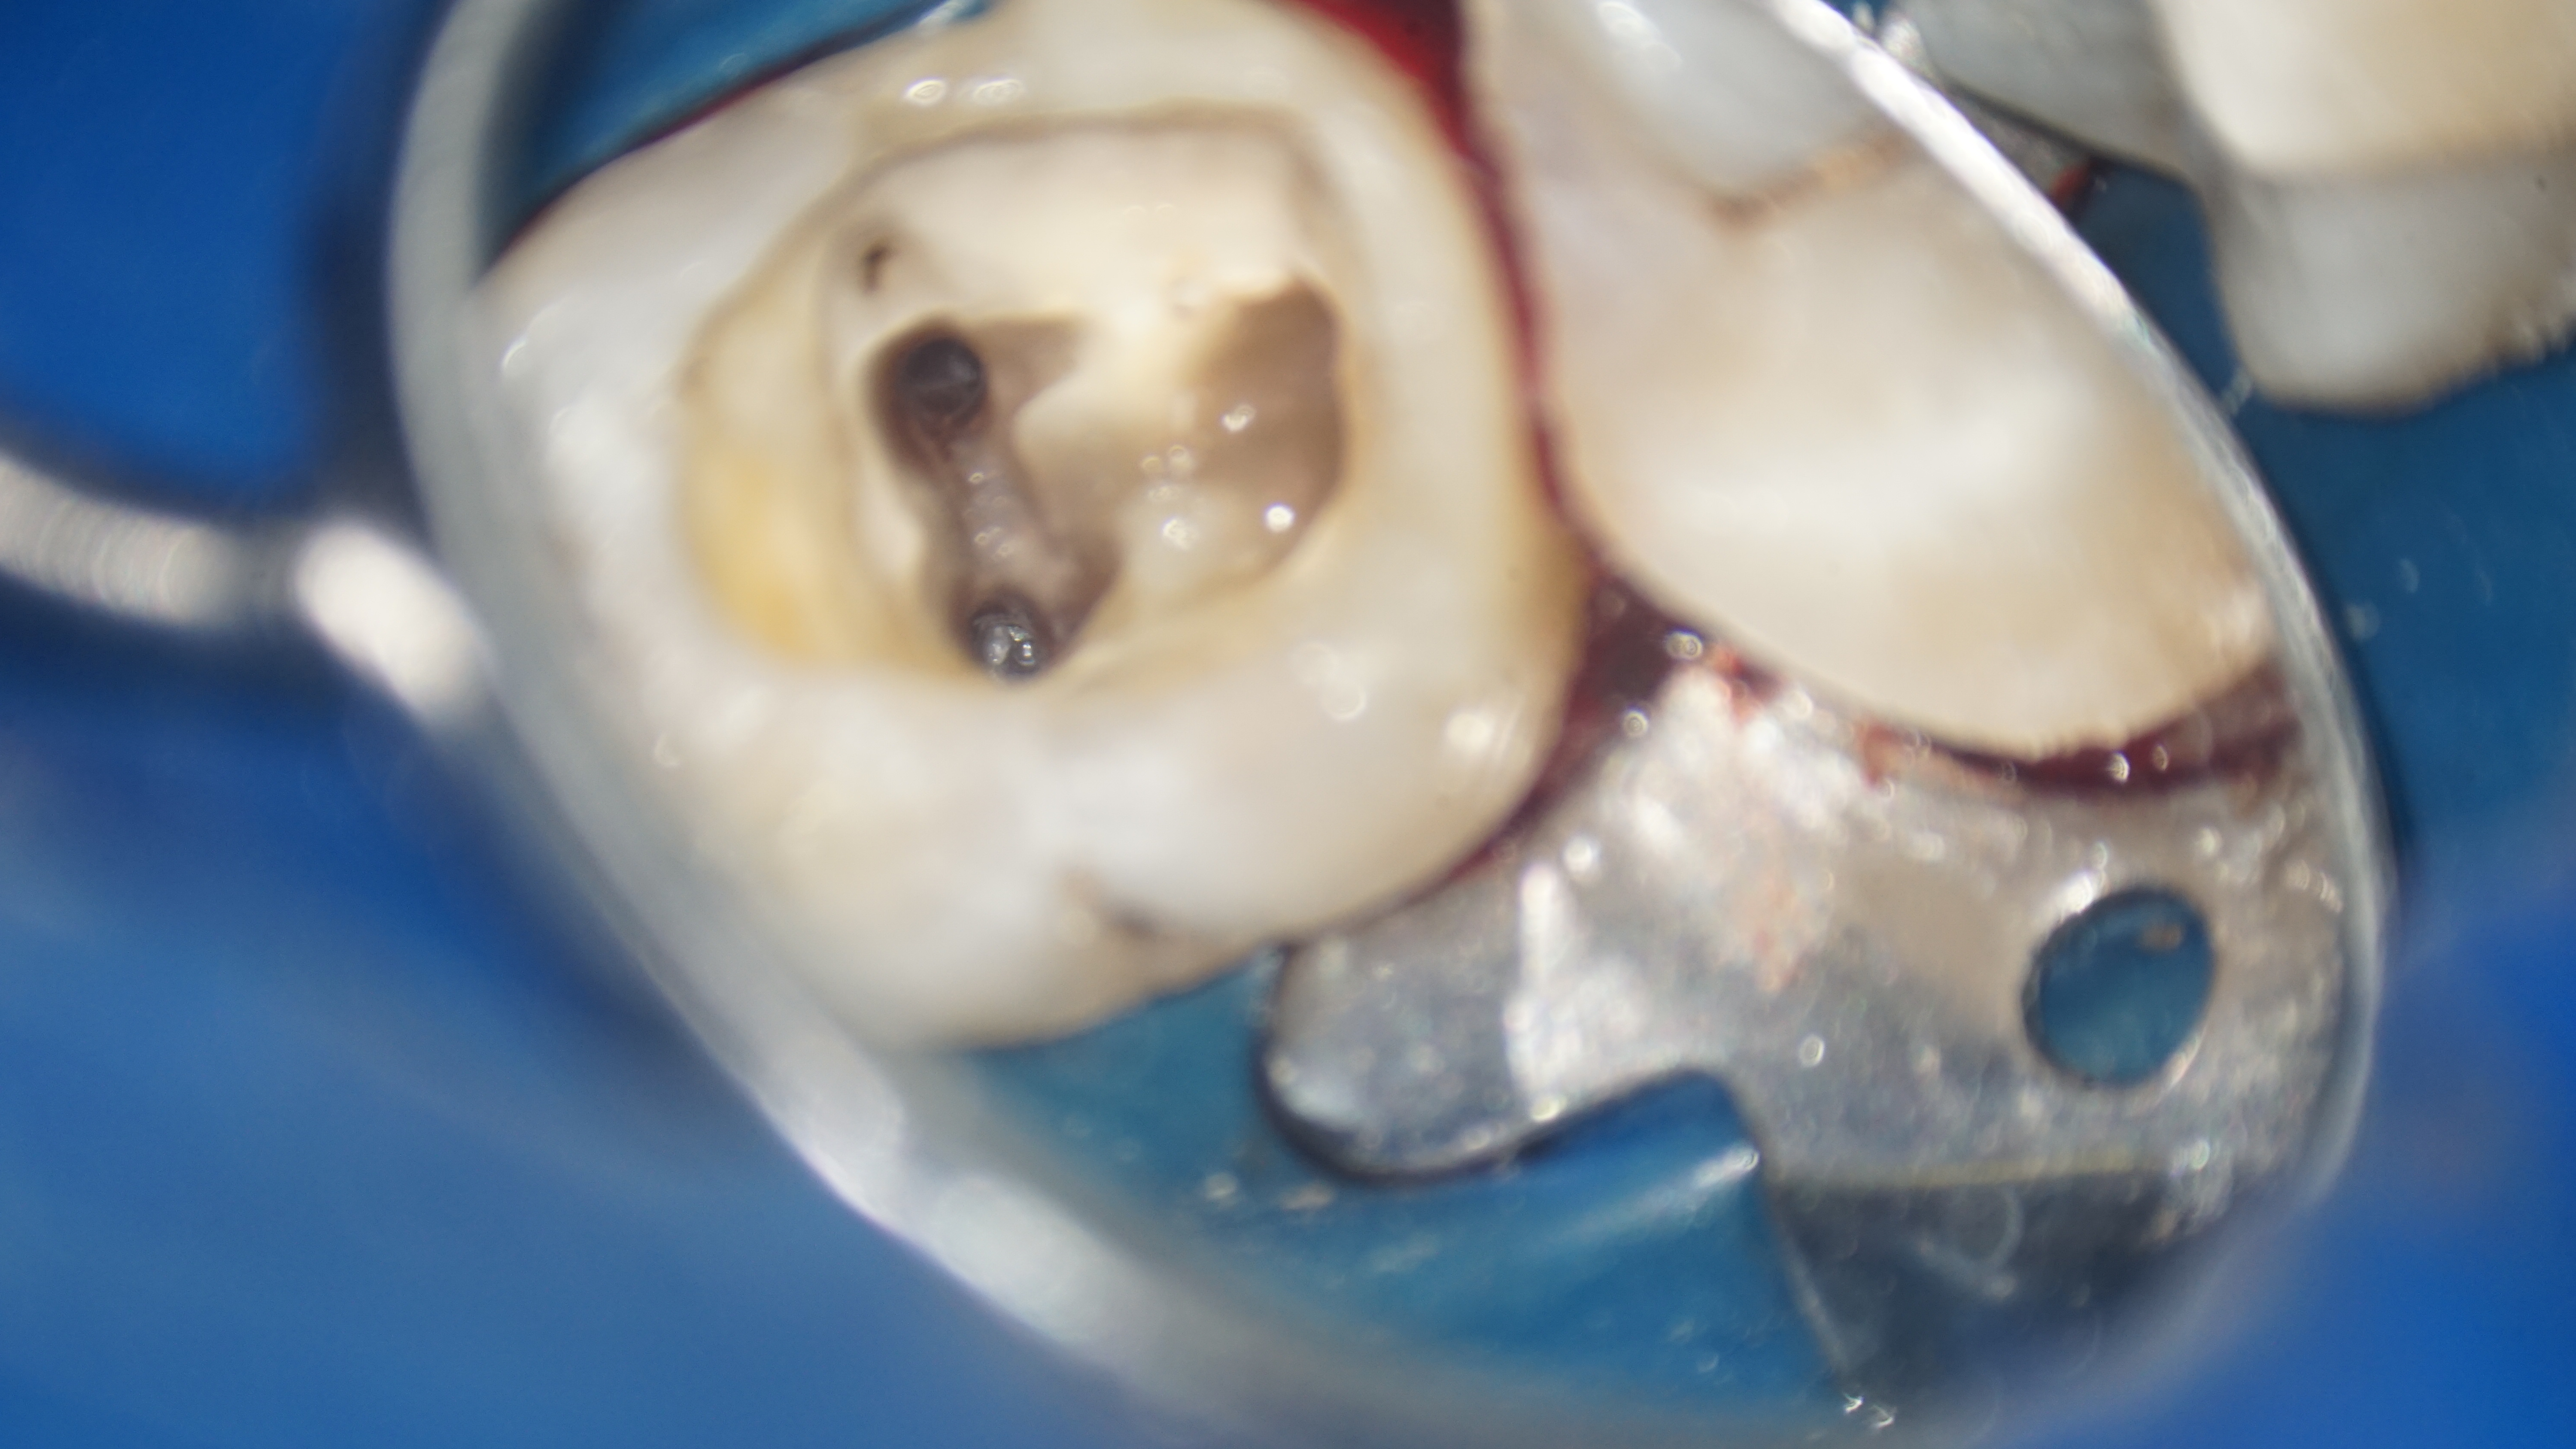

Cazul descris este al unui pacient care s-a prezentat la noi in clinică cu plângeri referitoare la dintele 46. Acest dinte a fost tratat anterior, în urma intervenţiei a rămas câte un fragment de ac în fiecare radacina.

Pacientul prezenta simptome de parodontită apicală, manifestate prin dureri și disconfort la masticatie. Parodontita apicală cronică reprezintă o inflamație persistentă la nivelul țesuturilor de la vârful rădăcinii dintelui, rezultată din infecția bacteriană al canalului radicular. După evaluarea clinică și radiografică, s-a constatat că fragmentele de ac separate accidental împiedicau vindecarea completă a infecției și a inflamației. Tratamentul endodontic inițial nu a fost suficient pentru a remedia problema.

Astfel, s-a decis refacerea tratamentului iniţial, fapt ce a implicat instrumentarea canalelor radiculare și curățarea lor adecvată, realizând bypass-ul (ocolirea) fragmentului din rădăcina mezială şi înlăturarea celui din rădăcina distală. După finalizarea procedurilor, pacientul a raportat dispariția simptomatologiei și ameliorarea disconfortului la masticatie.